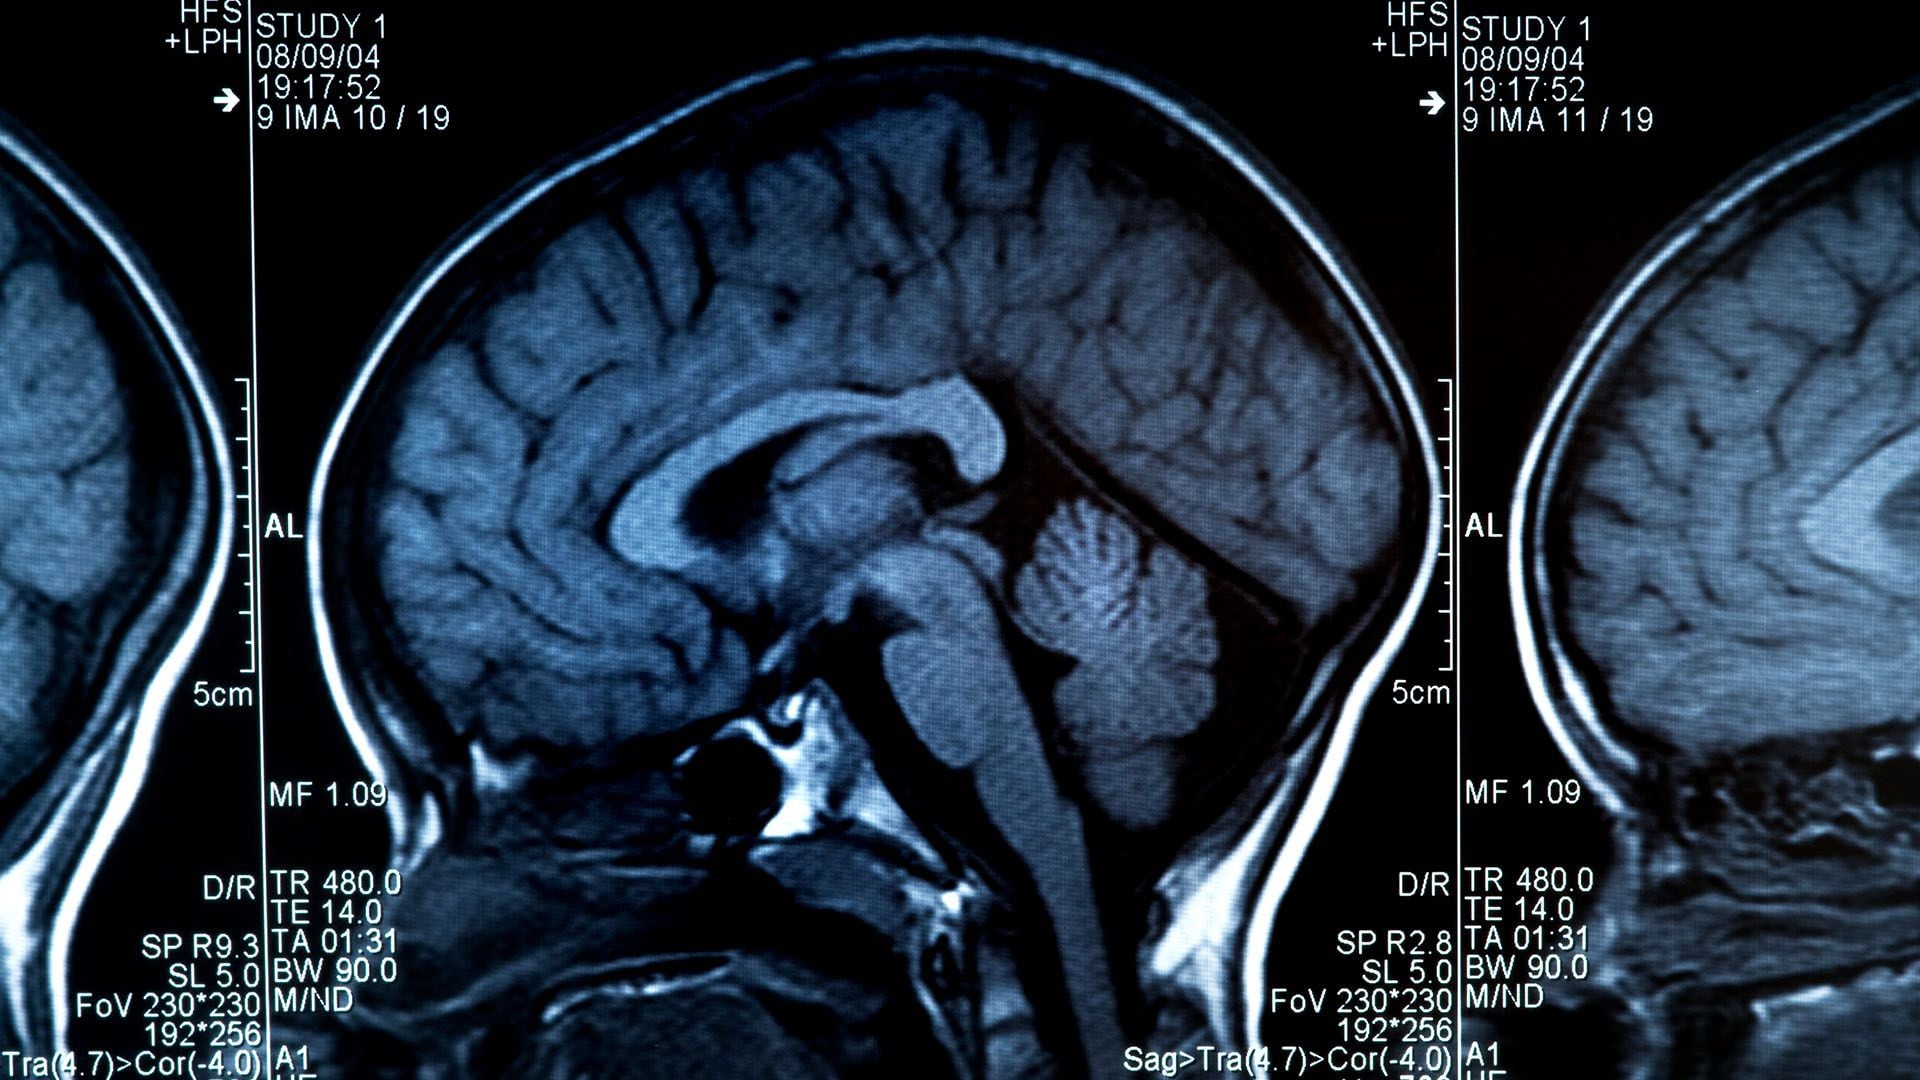

Más allá de las señales de alerta mencionadas, cada persona puede presentar síntomas diferentes y a la vez, la presencia de uno o varios de ellos no necesariamente indica la existencia de un tumor cerebral. Cuando un paciente llega con un cuadro sospechoso, el primer estudio de urgencia que se suele realizar es una tomografía de cerebro aunque el doctor Chaves nos aclaró que este estudio no es suficiente.

“El estudio ideal para descartar un tumor es una resonancia magnética de cerebro con y sin contraste. Y el diagnóstico final y definitivo se da por el estudio del tejido tumoral por un médico anátomo-patólogo. Esto se puede lograr tomando una pequeña muestra a través de una biopsia o con el análisis del tejido obtenido luego de una resección quirúrgica”, detalló.